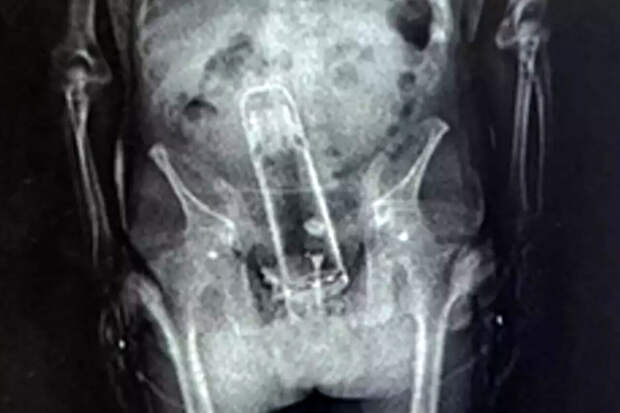

При стандартном рентгеновском осмотре сотрудники учреждения обнаружили в теле мужчины металлический предмет, который оказался термосом. По словам шерифа округа Полк Грейди Джаджа, "задержанный принес термос в тюрьму самым необычным способом".